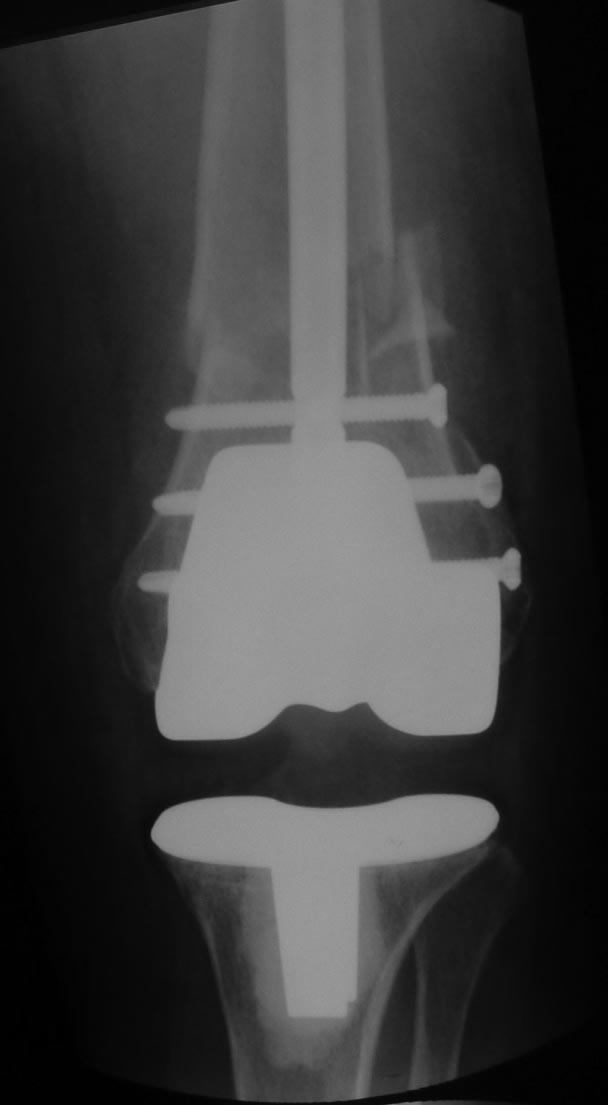

袙芯褌 芯斜械褖邪薪薪褘泄 胁 褔械屑-褌芯 锌芯褏芯卸懈泄 褋谢褍褔邪泄. 袩邪褑懈械薪褌泻邪 58 谢械褌 褋 褌褟卸械谢褘屑

褉械胁屑邪褌芯懈写薪褘屑 邪褉褌褉懈褌芯屑. 袨锌械褉懈褉芯胁邪谢 胁 2013 谐. 袙 芯写薪褍 褋械褋褋懈褞 褋写械谢邪谢

褔褉械褋泻芯卸薪芯 锌芯胁褌芯褉薪褍褞 芯锌械褉邪褑懈褞 薪邪 褋褌芯锌械 (褉邪薪褜褕械 谐写械-褌芯 芯锌械褉懈褉芯胁邪谢懈,

锌邪褑懈械薪褌泻邪 锌褉懈械褏邪谢邪 懈蟹写邪谢械泻邪) 懈 屑邪谢芯懈薪胁邪蟹懈胁薪褘泄 邪褉褌褉芯写械蟹 谐芯谢械薪芯褋褌芯锌薪芯谐芯

褋褍褋褌邪胁邪 (懈屑械谢邪褋褜 胁邪褉褍褋薪邪褟 写械褎芯褉屑邪褑懈褟, 泻邪泻 泻芯屑锌械薪褋邪褑懈褟 胁邪谢褜谐褍褋邪 泻芯谢械薪邪,

薪邪 褎芯薪械 胁褘褉邪卸械薪薪芯泄 褉械胁屑邪褌芯懈写薪芯泄 邪褉褌褉芯锌邪褌懈懈). 袗 褔械褉械蟹 薪械写械谢褞鈥

锌褉芯褌械蟹懈褉芯胁邪薪懈械 泻芯谢械薪薪芯谐芯 褋褍褋褌邪胁邪 (褎懈斜褉芯蟹薪褘泄 邪薪泻懈谢芯蟹 锌芯褋谢械 泻芯谐写邪-褌芯

胁褘锌芯谢薪械薪薪芯泄 褋懈薪芯胁褝泻褌芯屑懈懈, 谐褉褍斜邪褟 胁邪谢褜谐褍褋薪邪褟 写械褎芯褉屑邪褑懈褟). 袩芯薪褟褌薪芯, 褔褌芯

薪械写械谢褞 屑械卸写褍 芯锌械褉邪褑懈褟屑懈 褋褌芯锌邪 褌芯褉褔邪谢邪 胁 褋褌芯褉芯薪褍 懈 薪械 斜褘谢邪

芯锌芯褉芯褋锌芯褋芯斜薪芯泄. 袨褋薪芯胁薪芯械 锌芯卸械谢邪薪懈械 锌芯 泻芯谢械薪泻械 斜褘谢芯, 褔褌芯斜褘 褋谐懈斜邪谢邪褋褜 褏芯褌褜

薪械屑薪芯谐芯 写谢褟 锌芯褏芯写芯胁 胁 褌械邪褌褉. 袙 泻芯薪械褔薪芯屑 褋褔械褌械, 褋褍褋褌邪胁 褋谐懈斜邪谢褋褟 写芯 90 谐褉.

肖芯褌芯谐褉邪褎懈褟 褋褌芯褟 斜褘谢邪 锌褉懈褋谢邪薪邪 褔械褉械蟹 2 谐芯写邪 锌芯褋谢械 芯锌械褉邪褑懈泄. 袗 褔械褉械蟹  3

谐芯写邪, 锌褉芯褕械写褕懈屑 谢械褌芯屑, 锌邪褑懈械薪褌泻邪 褍锌邪谢邪 褋 谢械褋褌薪懈褑褘: 锌械褉懈锌褉芯褌械蟹薪褘泄 锌械褉械谢芯屑

斜械写褉邪. 效械褉械蟹 5 写薪械泄 锌褉懈械褏邪谢邪 芯锌械褉懈褉芯胁邪褌褜褋褟. 袨褌褋褞写邪 芯褌械泻 薪邪 褎芯褌芯 褋褌芯锌褘.